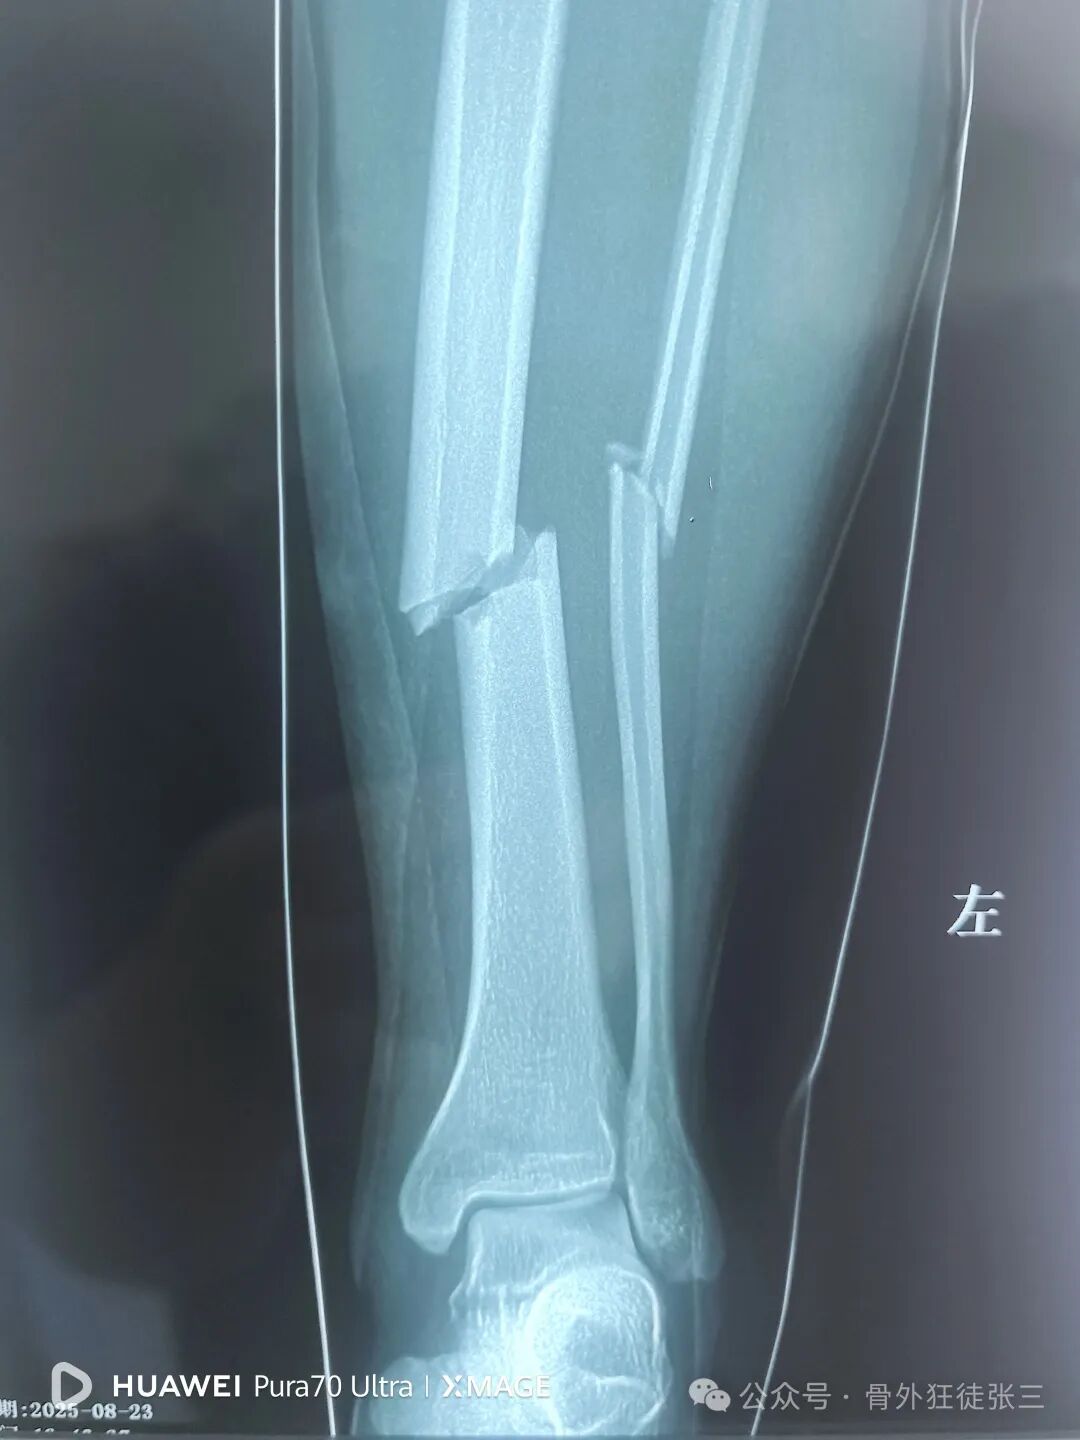

胫腓骨骨折

患者无法接受消肿后手术

要求急诊手术

早日下床

患者合理诉求

安排!